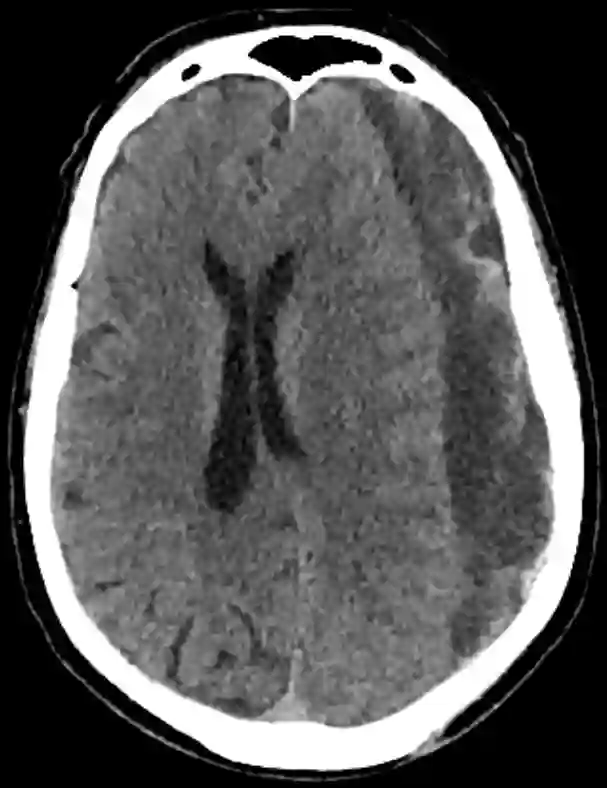

Chronisches Subduralhämatom mit subakuten Einblutungen

Darstellung eines chronischen Subduralhämatoms mit subakuten Einblutungen beidseits im axialen CT Bild.